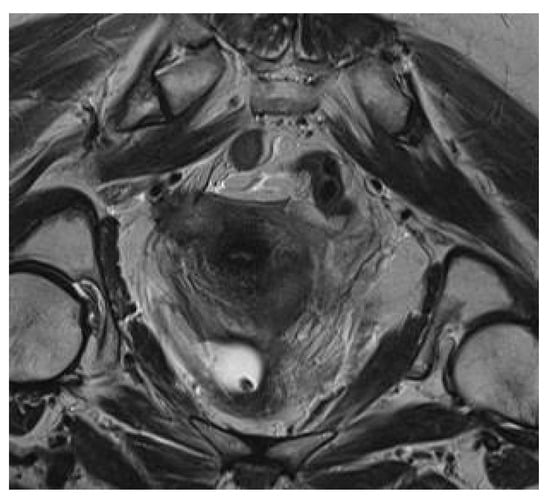

2. Case Report